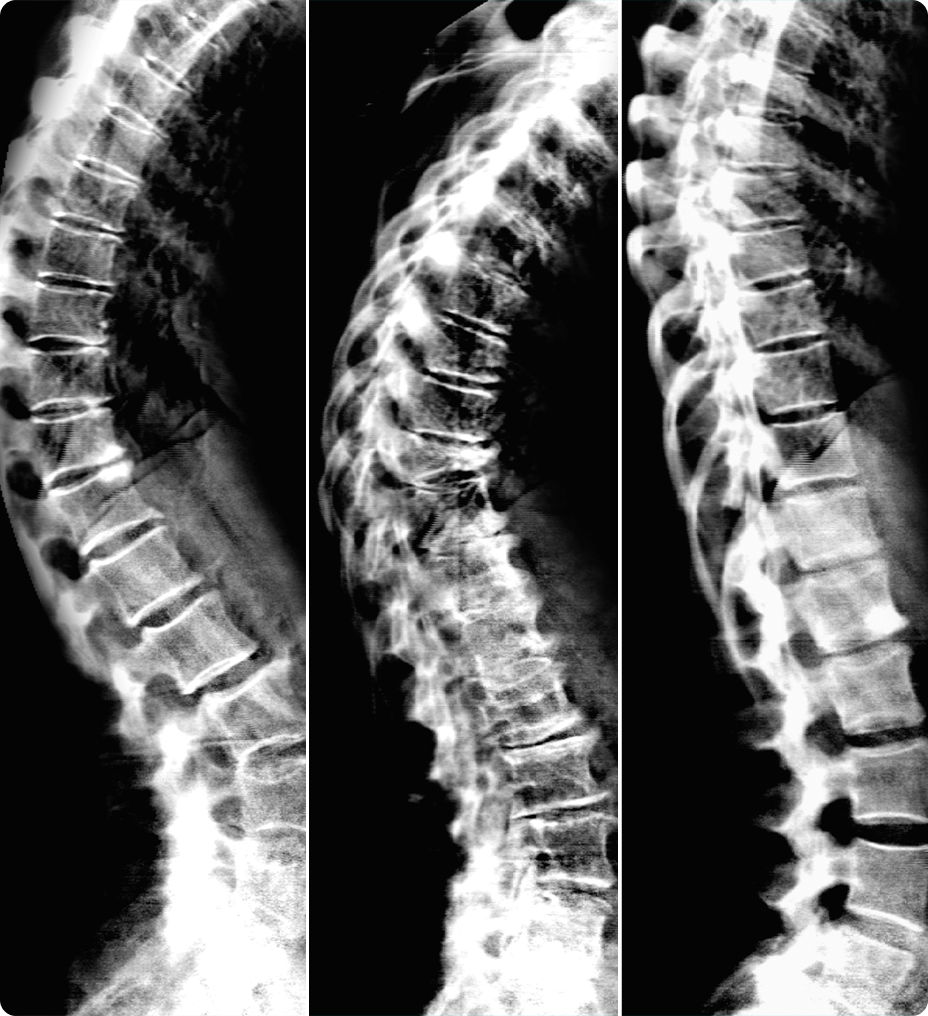

Daha net görüntüler daha kolay tanılar anlamına gelir ve derin öğrenme teknolojimiz AIR™ Recon DL ile olağanüstü kalitede görüntüleri daha hızlı elde edebilirsiniz. Çok çeşitli anatomiler için en net sonuçları sağlayarak MR görüntülerini görüntüleme biçiminizde devrim yaratır.

Ayrıca, göz yorgunluğunu azaltabilen okunması kolay, yüksek kaliteli taramalarla elde ettiğiniz görüntülerin kalitesinden daha emin olarak oluşturulan raporların daha iyi bir genel deneyime sahip olmasını sağlayabilirsiniz.